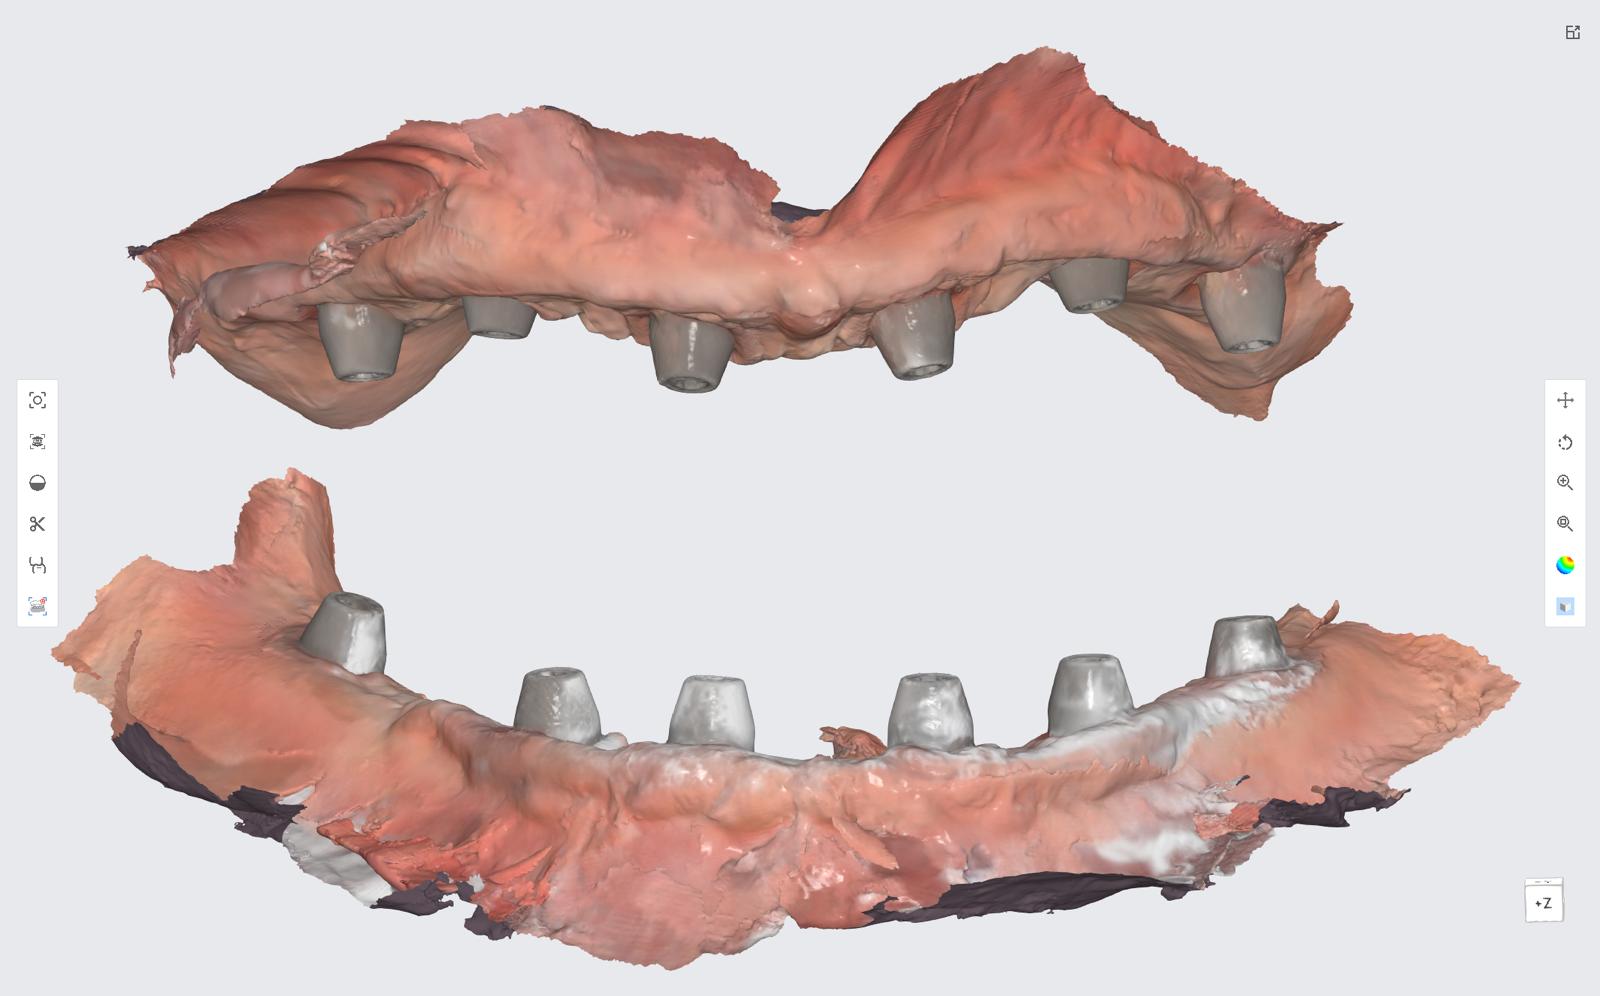

The revolutionary All-on-X (AOX) model-less workflow has become a reality through seamless integration of state-of-the-art technologies: interactive implant planning software, guided surgery systems, intraoral scanning (IOS), advanced 3D printing, and photogrammetry. Our innovative CAD-CAM protocols dramatically streamline the treatment process, reducing appointment frequency, chair time, and prosthetic delivery intervals. We've pioneered multiple digital workflows that ensure precise implant position recording and bite capture for full-arch implant rehabilitation.

The latest breakthroughs in 3D printing technology and materials enable same-day provisional restoration with unprecedented predictability. Clinicians can now consistently produce highly accurate temporaries that achieve perfect fit on multi-unit abutments (MUAs), whether using freehand or guided surgical approaches.